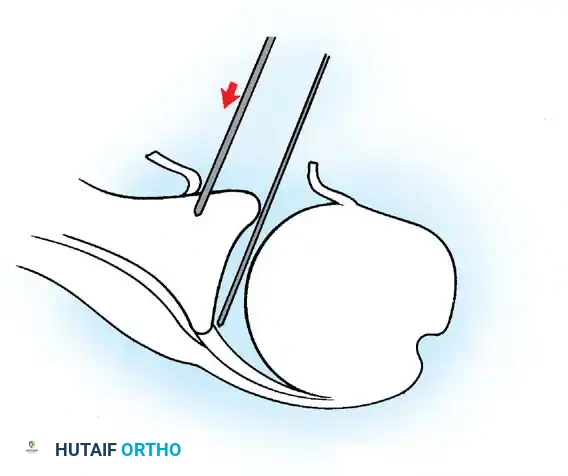

- Anchor Placement: Suture anchors (typically 3 to 4) are placed along the articular margin of the anteroinferior glenoid (from the 5:30 to 3:00 positions for a right shoulder). Anchors must be inserted at a 45-degree angle to the articular surface to maximize pullout strength and avoid joint penetration.